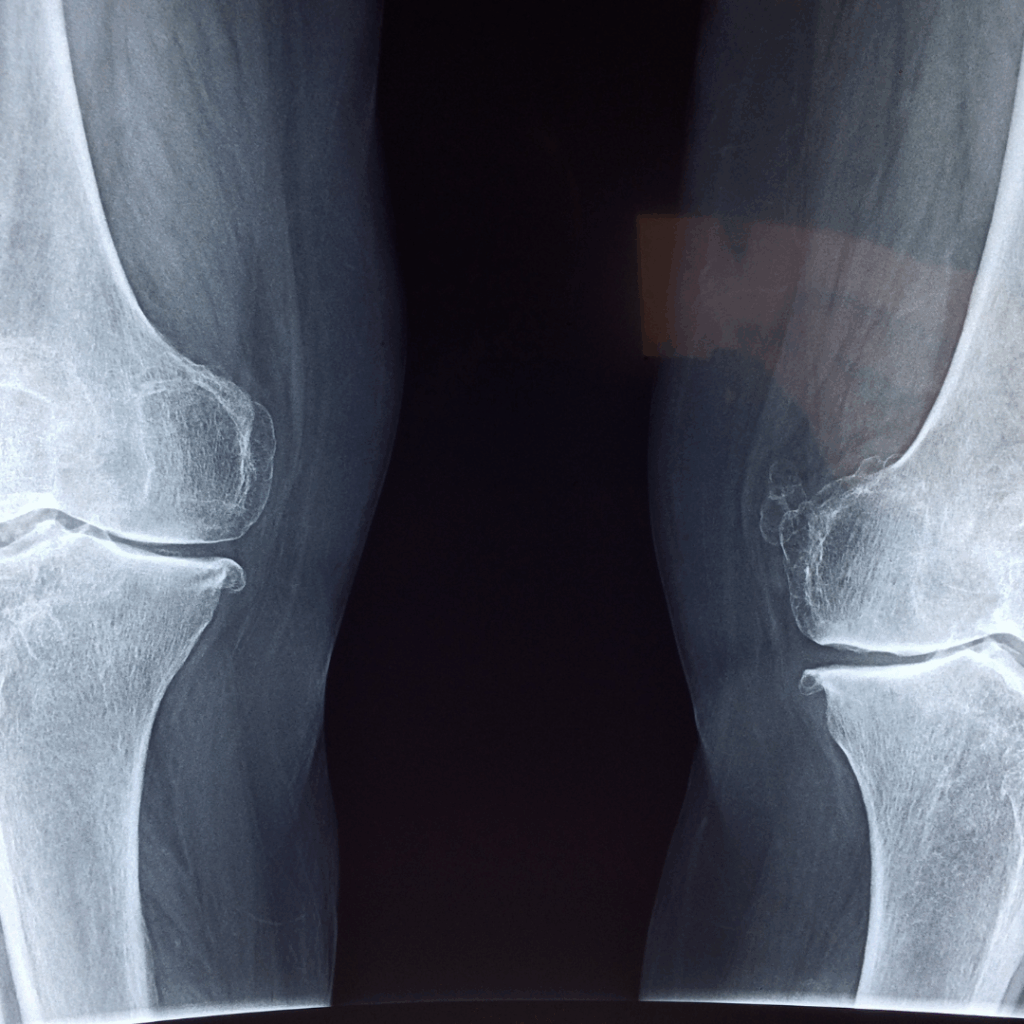

Effective recovery follows accurate diagnosis. Diagnosis is by imaging techniques or through clinical evaluation, and can identify where the root of the pain or injury lies. A treatment plan is then initiated using a stepwise approach that focuses on treatment strategies and prevention strategies for the future.

- Accurate Diagnosis – By way of X-ray or MRI or through physical assessment, the cause of the discomfort can be determined.